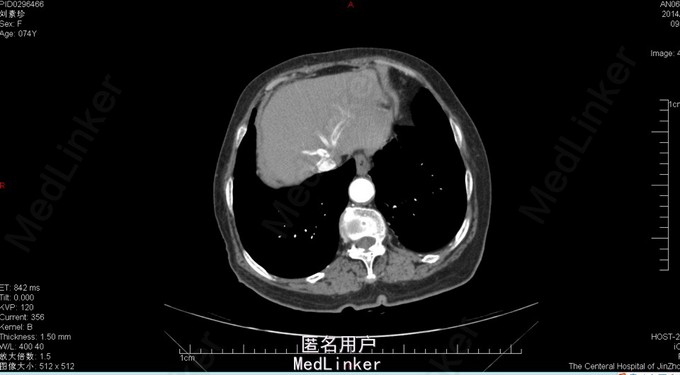

胆囊十二指肠瘘,结石性幽门梗阻

74岁女患,上腹部疼痛伴恶心呕吐3天。 3天前患者开始出现上腹部不适疼痛,同时伴有恶心、呕吐。呕吐物为胃内容物,餐后严重。患者在家自行消炎治疗,症状逐渐加重。患者为求进一步诊治来我院。 既往胆囊结石病史。

查体:上腹部压痛明显,伴反跳痛及肌紧张。 腹部ct:十二指肠内结石?(回忆部分)

胆囊十二指肠瘘,结石性幽门梗阻,腹膜炎。 给予患者胆囊切除+十二指肠修补局部引流?(记不太清)患者术后恢复还可以,顺利出院。

此病例为普外科轮转期间收集影像资料所得,病例内细致资料不全面,不能详尽分享。但此种病例少见,影像资料清晰,值得学习探讨。 欢迎普外专业同道探讨患者手术方式。让大家共同进步。